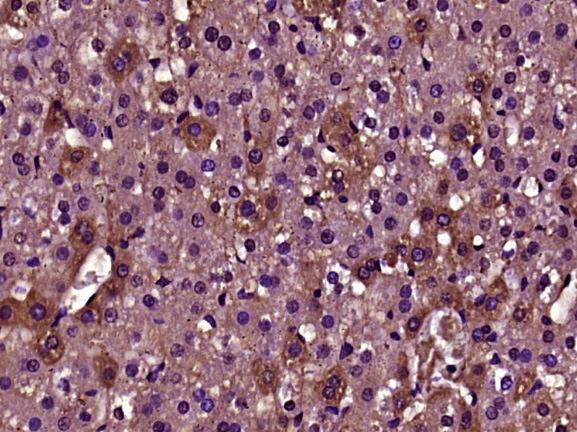

Paraformaldehyde-fixed, paraffin embedded (Rat liver); Antigen retrieval by boiling in sodium citrate buffer (pH6.0) for 15min; Block endogenous peroxidase by 3% hydrogen peroxide for 20 minutes; Blocking buffer (normal goat serum) at 37°C for 30min; Antibody incubation with (DENND1A) Polyclonal Antibody, Unconjugated (bs-14269R) at 1:400 overnight at 4°C, followed by operating according to SP Kit(Rabbit) (sp-0023) instructionsand DAB staining.

Paraformaldehyde-fixed, paraffin embedded (Rat brain); Antigen retrieval by boiling in sodium citrate buffer (pH6.0) for 15min; Block endogenous peroxidase by 3% hydrogen peroxide for 20 minutes; Blocking buffer (normal goat serum) at 37°C for 30min; Antibody incubation with (DENND1A) Polyclonal Antibody, Unconjugated (bs-14269R) at 1:500 overnight at 4°C, followed by a conjugated secondary (sp-0023) for 20 minutes and DAB staining.